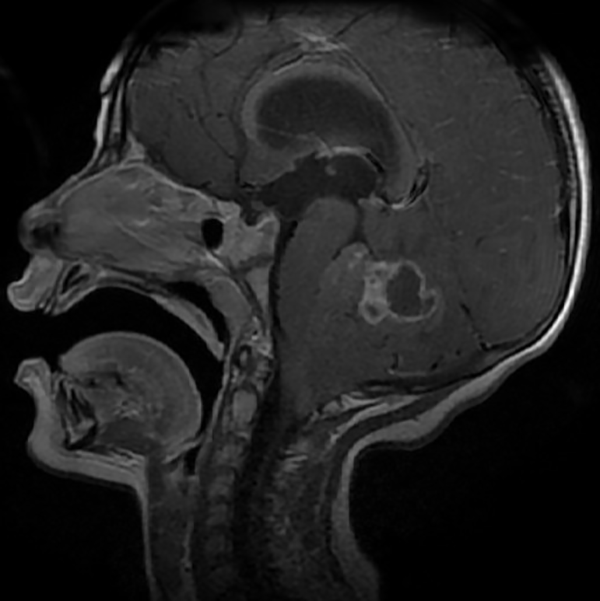

En resonancia magnética (RM) de cerebro se observa tumoración heterogénea sólida o sólido-quística con áreas de hemorragia, quistes y calcificaciones, que capta contraste en forma variable. (Fig. 1, 2, 3, 4). El patrón en espectroscopía se caracteriza por presentar pico de Colina (Cho) y descenso de N-Acetilaspartato (NAA).

Fig 4:

RM corte sagital, secuencia T2. Se observa neoformación, solido-quística, iso-hiperintensa heterogénea de bordes irregulares en la topografía del VI ventrículo que ocupa la totalidad del mismo. Se proyecta caudalmente a través del foramen magno. Se evidencia colapso del VI ventrículo, desplazamiento del tronco cerebral hacia anterior y abombamiento del cuerpo calloso debido a la hidrocefalia obstructiva.